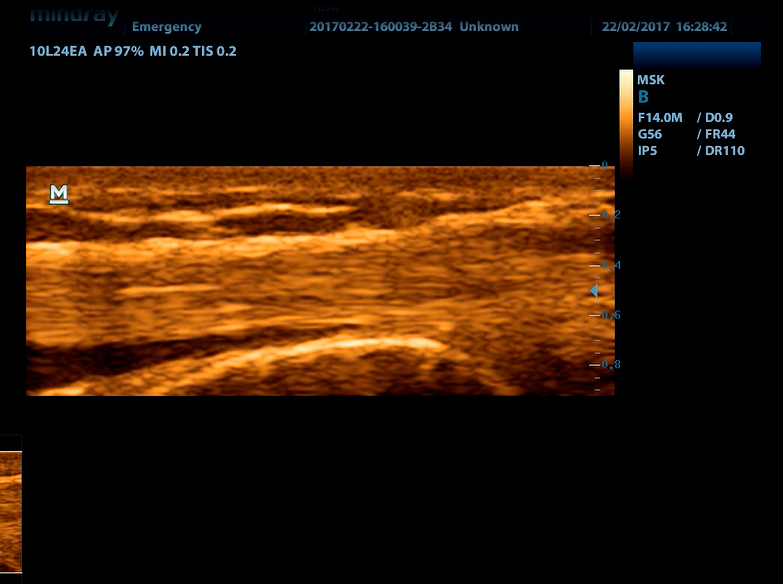

Линейный датчик высокочастотный 10L24EA (8.0/10.0/12.0/14.0/Н10.0/Н12.0 МГц, 24 мм)